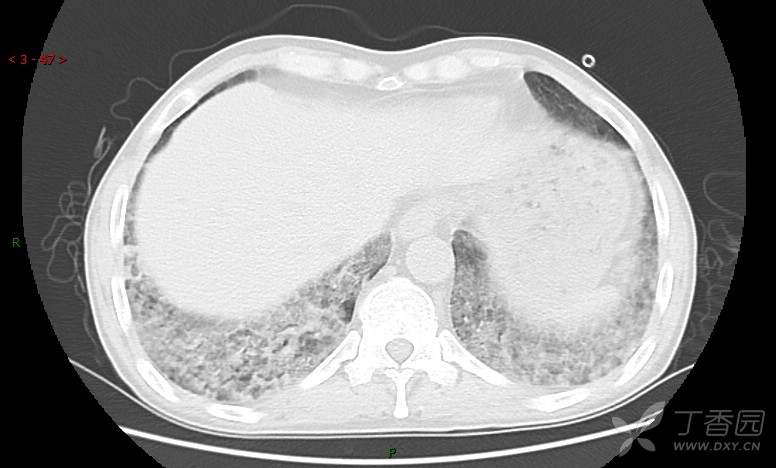

地图+铺路石征=PAP?那升高的CEA怎么说(病例3连发,附其他2例链接)

患者男,42岁,咳嗽半年余,加重伴憋喘2月余。

患者半年余前无明显诱因出现间断咳嗽,干咳为主,偶咳少量黄白痰,剧烈咳嗽或运动后可出现轻度憋喘,无高热、脓臭痰,无胸痛、咯血及晕厥,无低热乏力及盗汗,无心前区压榨感及夜间阵发性呼吸困难,初未在意,未予正规诊治。2月余前患者自觉上述症状较前加重,咳嗽、憋喘明显,黄白色粘痰略有增多,伴有发热,热前伴有畏寒、寒战,体温最高达38.9℃,先后就诊多家医院,入住重症监护室,未行气管插管,考虑“重症肺炎”,给予“美罗培南、复方磺胺甲噁唑”等药物抗感染,“卡泊芬净”抗真菌,并给予“甲泼尼龙”等药物治疗35天,经治疗后症状好转于2018-04-02出院。患者自出院后仅应用中药治疗(具体不详),并给予家庭氧疗,平素仍有间断咳嗽,咳少量黄白色粘痰,活动后憋喘明显,活动耐量差,以卧床为主。